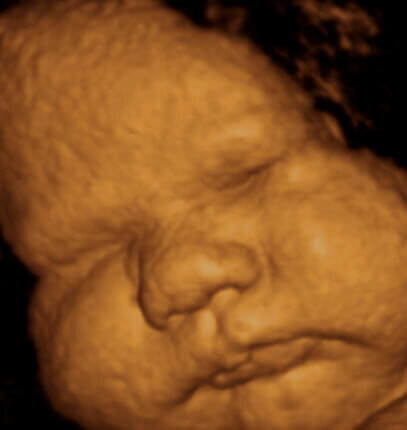

39-40-я НЕДЕЛИ ПОСЛЕ ЗАЧАТИЯ

Все органы и системы полностью зрелые, достаточно подкожных жировых клеток, развитые органы чувств, скоординированы движения. На коже ребёнка имеется совсем небольшое количество смазки, которая уже не сможет защитить её от воздействия околоплодной жидкости. Если по каким-то причинам роды задерживаются, то уменьшение смазки ведёт к мацерации незащищённых мест, в первую очередь появляются «банные» стопы и ладошки или «руки прачки». Ребенок прибавляет в весе вплоть до самого рождения. Пушок сохраняется только на плечиках. Ноготки выступают над фалангами пальцев. Наружные половые органы уже развиты — у мальчиков — яички в мошонке, у девочек — большие половые губы прикрыли малые. Когда малыш будет готов выходить, его мозг пошлет цепочку химических сигналов, вследствие чего повысятся уровни определенных гормонов в организме матери. Результатом этого обычно становится отхождение вод и начало родовых схваток. Рост: 51,2 – 51,7 см Вес: 3,46 – 3,60 кг Материал из Википедии — свободной энциклопед